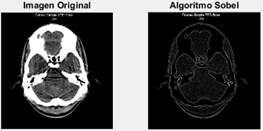

La mayoría de las investigaciones se dedican en la segunda etapa del procesamiento de imágenes donde se seleccionó los más utilizados y que mejores resultados ofrecen como la umbralización, el crecimiento de regiones y para terminar con esta etapa se implementaron cuatro algoritmos detectores de bordes el Canny, Prewitt, Sobel y Roberts. La primera etapa de procesamiento de imagen que se conoce como pre-procesamiento se implementaron los algoritmos de binarización, normalización, en escala de gris, filtro espacial, filtro pasa bajo, filtro mediana y Filtro Butterwort. Estos algoritmos son infalibles en la primera etapa y la última etapa se implementó los algoritmos de extracción de puntos y Transformada de Hough.

A continuación, se muestran las características y los resultados de los algoritmos utilizados en las Figura 4, Figura 5 y Figura 6 y se realiza una valoración sobre los aciertos de cada uno de ellos en el proceso de procesamiento de imágenes en las Tabla 1, Tabla 2 y Tabla 3, para la muestra se utilizó la herramienta de Matlab 2017 Figura 7:

En el procesamiento de imágenes se trabajó con varios algoritmos comportándose cada uno de ellos de diferentes maneras en correspondencia al tiempo de procesamiento y acierto en el trabajo que se necesitaba como se muestran en las siguientes imágenes A, B C, resaltado que los algoritmos Isodata, y Otsu su diferencia entre el acierto y el tiempo de ejecución son similares véase en la Figura 8, en el procesamiento basado en regiones sucede de igual manera con Cr y DFR.